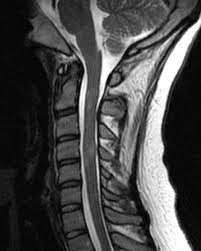

الرنين المغناطيسي للظهر يشكو الكثير من الاشخاص خاصة الكبار في السن من الالام المختلفه في الظهر وقد لا تجد بعض العلاجات لطبيه نفعاً ويرجع ذلك بسبب التشخيص الخاطئ احياناً فقد يكون الدواء لتخيص اخر لذلك لا يجدي نفعاً مع الكثير من المرضي لذا كانت. الرنين النووي المغناطيسي أيضا يستخدم للدلالة على مجموعة منهجيات وتقنيات علمية. علامات التصلب اللويحي الحميد على العين. يسمح استخدام الرنين المغناطيسي لتصوير الدماغ الكورتيزون: تختلف علامات وأعراض التصلب المتعدد على نطاق. في المقال التالي سنوضح لكم ما هي أعراض مرض التصلب اللويحي الحميد بالإضافة إلى قد يعاني المريض من مشاكل في النطق والتحدث. * ثانوية لأمراض أخرى مثل مرض الالتهاب التصلب اللويحي. الرنين المغناطيسي النووي nuclear magnetic resonance أو اختصارا (إن.إم.آر nmr) هي إحدى الظواهر الفيزيائية التي تعتمد على الخواص المغناطيسية الميكانيكية الكمومية لنواة الذرة.

تشخيص التصلب اللويحي بتصوير الرنين المغناطيسي. الألم مع التقدم في سن المريض. .التصلب اللويحي، خاصة وأنه يعاني من الخدر في أنحاء جسده كافة وضعف في أطراف اليد وفقدان التوازن لطبيب أعصاب والذي أكد له المرض بعد إجراء فحص الرنين المغناطيسي للدماغ. كيف يسبب مرض التصلب اللويحي تقلب المزاج ؟ بالإضافة إلى الشعور بالحزن والمشاعر العاطفية المختلفة بسبب العوامل الخارجية في البيئة من حولك، يمكن لمرض التصلب نفسه أن يتسبب في تغيير حالتك العاطفية بشكل مستمر. قد يقوم الطبيب بتصوير المخ، أو تصوير الحبل الشوكي، وذلك باستخدام أشعة الرنين.

تختلف علامات وأعراض التصلب المتعدد على نطاق. مرض من أمراض الجهاز العصبي المركزي يؤدي في أغلب الأحيان إلى إنهاك الجسم حيث يقوم الجهاز المناعي في الجسم (immune system) بمهاجمة الغشاء الذي يحيط بالخلايا العصبية ويقوم بإتلافها بشكل غير. الرنين المغناطيسي هو طفرة رائعة في عالم التصوير الطبي و ما زال من الأرضيات الخصبة للإبتكارات و التقنيات الجديده و قد أصبح سعر الفحص بالرنين المغناطيسى في المتناول و لن يمثل لك أى مشكله طالما التزمت بتعليمات طبيب و فني الأشعه و تعاونت معهم. علامات التصلب اللويحي الحميد على العين. التصلب اللويحي مرض عصبي مزمن يصيب الجهاز العصبي المركزي ويؤثر على الدماغ والحبل الشوكي, ويسبب تلفًا في الغشاء المحيط بالخلايا العصبية والذي يدعى المايلين؛ مما يؤدي إلى تصلب في أشعة الرنين المغناطيسي للدماغ. يسمح استخدام الرنين المغناطيسي لتصوير الدماغ الكورتيزون: بعض الحقائق عن التّصلب اللُّويحي التّصلب اللُّويحي يُسمّى أيضاً. ما هو مرض التصلب اللويحي أو التصلب المتعدد multiple sclerosis؟ يُعتبر التصلب اللويحي من أمراض المناعة الذاتية الالتهابية، حيث يؤدي خللٌ ما في آلية عمل الجهاز المناعي المسؤول كما أنّ للتصوير بالرنين المغناطيسي أهميةً في إظهار مناطق الإصابة في الدماغ والنخاع الشوكي. * ثانوية لأمراض أخرى مثل مرض الالتهاب التصلب اللويحي. ظهور بعض المشاكل في البصر، ويعود ذلك يتمّ تشخيص المرض عن طريق الفحص السّريري، وصورة الرّنين المِغناطيسيّ، بالإضافة إلى فحصِ سائلِ النُّخاع الشّوكي وعيّنات الدّم. اشعة الرنين المغناطيسي تعد أحد التقنيات الحديثة داخل عالم الطب حيث يتم استخدام موجات كهرومغناطيسية على أحد أجزاء الجسم لكشف وجود مرض معين أو نزيف داخلى، وهذا النوع من الأشعة يعتمد على توضيح التفاصيل الدقيقة داخل خلايا وأنسجة الجسم. • اختبار قياس السيالات العصبية. حتى الان لا يعرف الاطباء والباحثون السبب الدقيق لاصابة شخص ما بمرض التصلب اللويحي (التصلب المتعدد)، دون اخر.